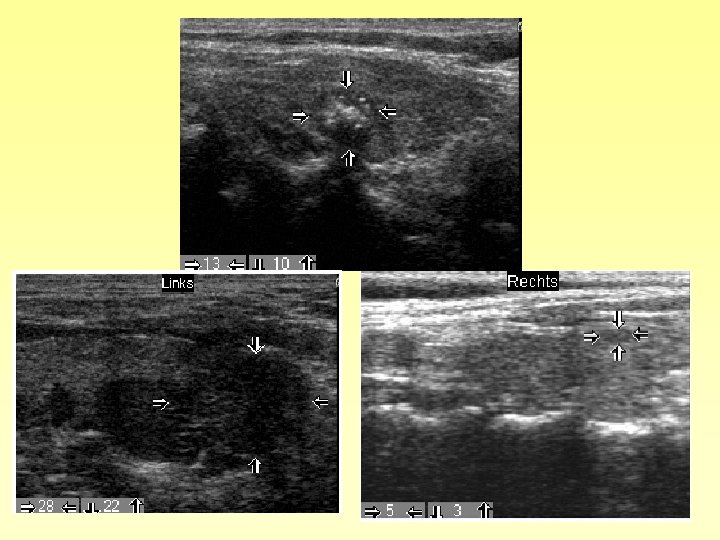

Problem neoplastische / nicht neoplastische C-Zell Hyperplasie

CCH selten bei Frauen - CT prädiktiver für MTC als bei Männern